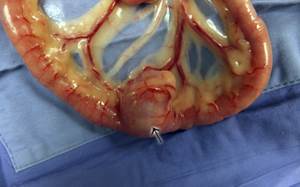

Аденокарцинома является самой распространенной опухолью кишечника. Чаще всего располагается в двенадцатиперстной кишке, толстом отделе кишечника и прямой кишке. Опухоль характеризуется быстрым, крайне агрессивным ростом, частым метастазированием в регионарные лимфатические узлы, печень и легкие. На момент обращения в ветеринарную клинику примерно у половины животных уже развиваются метастазы.

Аденома кишечника реже встречается у собак и обычно представлена полипоидными образованиями в толстом отделе кишечника и прямой кишке. Опухоль является доброкачественной.

Лейомиома и лейомиосаркома – опухоли, происходящие из гладкой мускулатуры кишечника. Выявляются в тонком отделе кишечника, слепой кишке. У половины собак развивается локальный перитонит при разрыве этих опухолей. Характерно частое метастазирование.